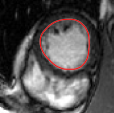

V-C LV and RV Segmentation: Quantitative Comparison to Commercial Software

We show experiments demonstrating the main use of our algorithm: in improving the prediction step of interactive segmentation methods. We show that less interaction is needed with our approach than a recent and widely used commercial cardiac segmentation software, Segment from Medviso [15, 44]. We perform quantitative assessment of the tracking performance of our method and compare it to Medviso. The evaluation was carried out on publicly available data sets, the MICCAI Left Ventricle Dataset [37] and the MICCAI Right Ventricle Dataset [25]. The validation dataset from [37] consists of 15 sets of cardiac cine-MRI images. Each set contains 6 to 20 2D slices from a 3D image, with each slice having 20 images of the cardiac phases. Similarly, the data set [25] contains 16 sets of cardiac cine-MRI images, each containing about 10 slices of 20 phases each. These data sets contain ground truth segmentations for left and right ventricles respectively (unfortunately ground truth for both the LV and RV is not available on a single dataset that we are aware of). Both methods start with the same initially correct segmentation, and subsequent frames are segmented via propagation. No manual interaction is used as we wish to show that our method would require less interaction. The regularity parameter in our method is found by choosing so that the results are closest to ground truth in a few training cases. The same parameter is then used for all other cases.

Figures 8 and 9 shows some sample tracking results of the proposed method and Medviso on full cardiac cycles of two different cases on both the LV dataset and the RV dataset. The ground truth (yellow) is superimposed when available. A summary of the results on the entire datasets is shown in Table I. The accuracy with respect to ground truth is measured using average perpendicular distance (APD) and dice metric (DM) for left ventricle, and Hausdorff distance (HD) and DM for the right ventricle. These metrics are chosen since they are the standard ones used on these datasets. Both qualitative and quantitative results show that our proposed method leads to more accurate segmentation of the ventricles and thus leads to less interaction than segmentation propagation schemes in than Medviso.